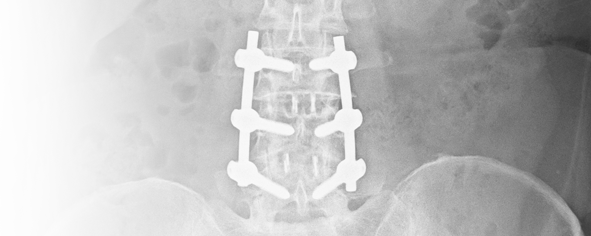

傳統手術的另一個可能併發症是由於椎突、椎板甚至於椎關節因減壓手術咬除後,造成脊椎穩定度不足,椎體間距 減少或脊椎滑脫造成神經壓迫等。 為了減少這類的問題發生,目前醫師常會建議同時做鈦合金椎體間支架固定融合 術(cage interbody fusion),及鈦合金骨釘固定。 由於新的固定器材(鈦合金椎體間支架,或PEEK材質支架)的使用 確實能減少上述的併發症的發生, 目前許多脊椎醫師均推薦此手術,但為了裝置固定器材手術的侵犯性更大,且手 術恢復時間仍長,目前我們大都保留在嚴重椎間盤突出,或併有嚴重狹窄或有關節變形的患者。椎體間支架(一節椎 間盤需兩顆支架,約七萬元)或人工椎間盤(一節需數十萬元)等器材健保並不給付,需要的費用頗高。